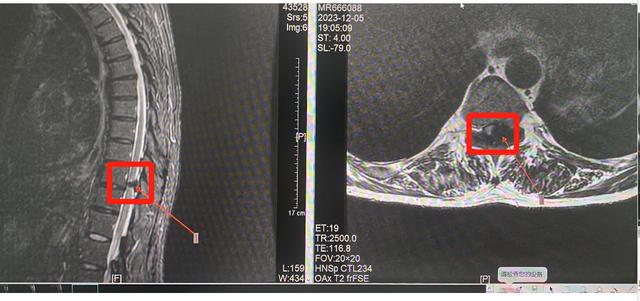

术前CT和磁共振,红箭头所示压迫病灶